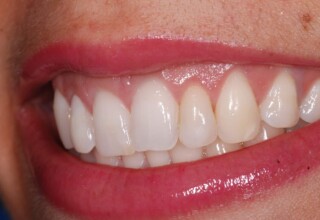

Restoration of bilateral diastemas between central and lateral incisors.

Diastemas were created mainly because of narrow laterals. After orthodontic treatment was finalized, the diastemas were closed with two composite resin restorations.